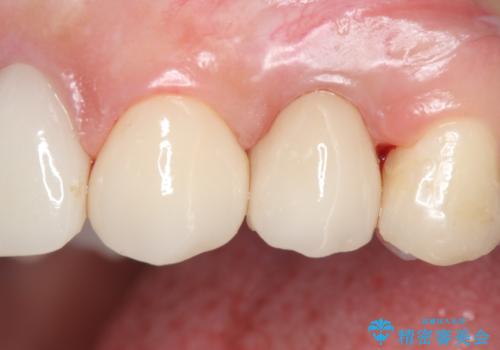

挺出終了後は歯肉切除および骨外科により歯周組織を整え、オールセラミッククラウンによる補綴を行いました。

オールセラミッククラウン(エコノミー)について

オールセラミッククラウン(エコノミー)はスタンダード以上と違い、一塊となっているため欠けてしまうリスクが低いのが特徴です。

しかしその反面選択できる色の種類が少なく、色合いも単調であるという欠点もありますが、今回のケースのように前後の歯がクラウンの場合などでは十分に審美的な補綴が可能となります。